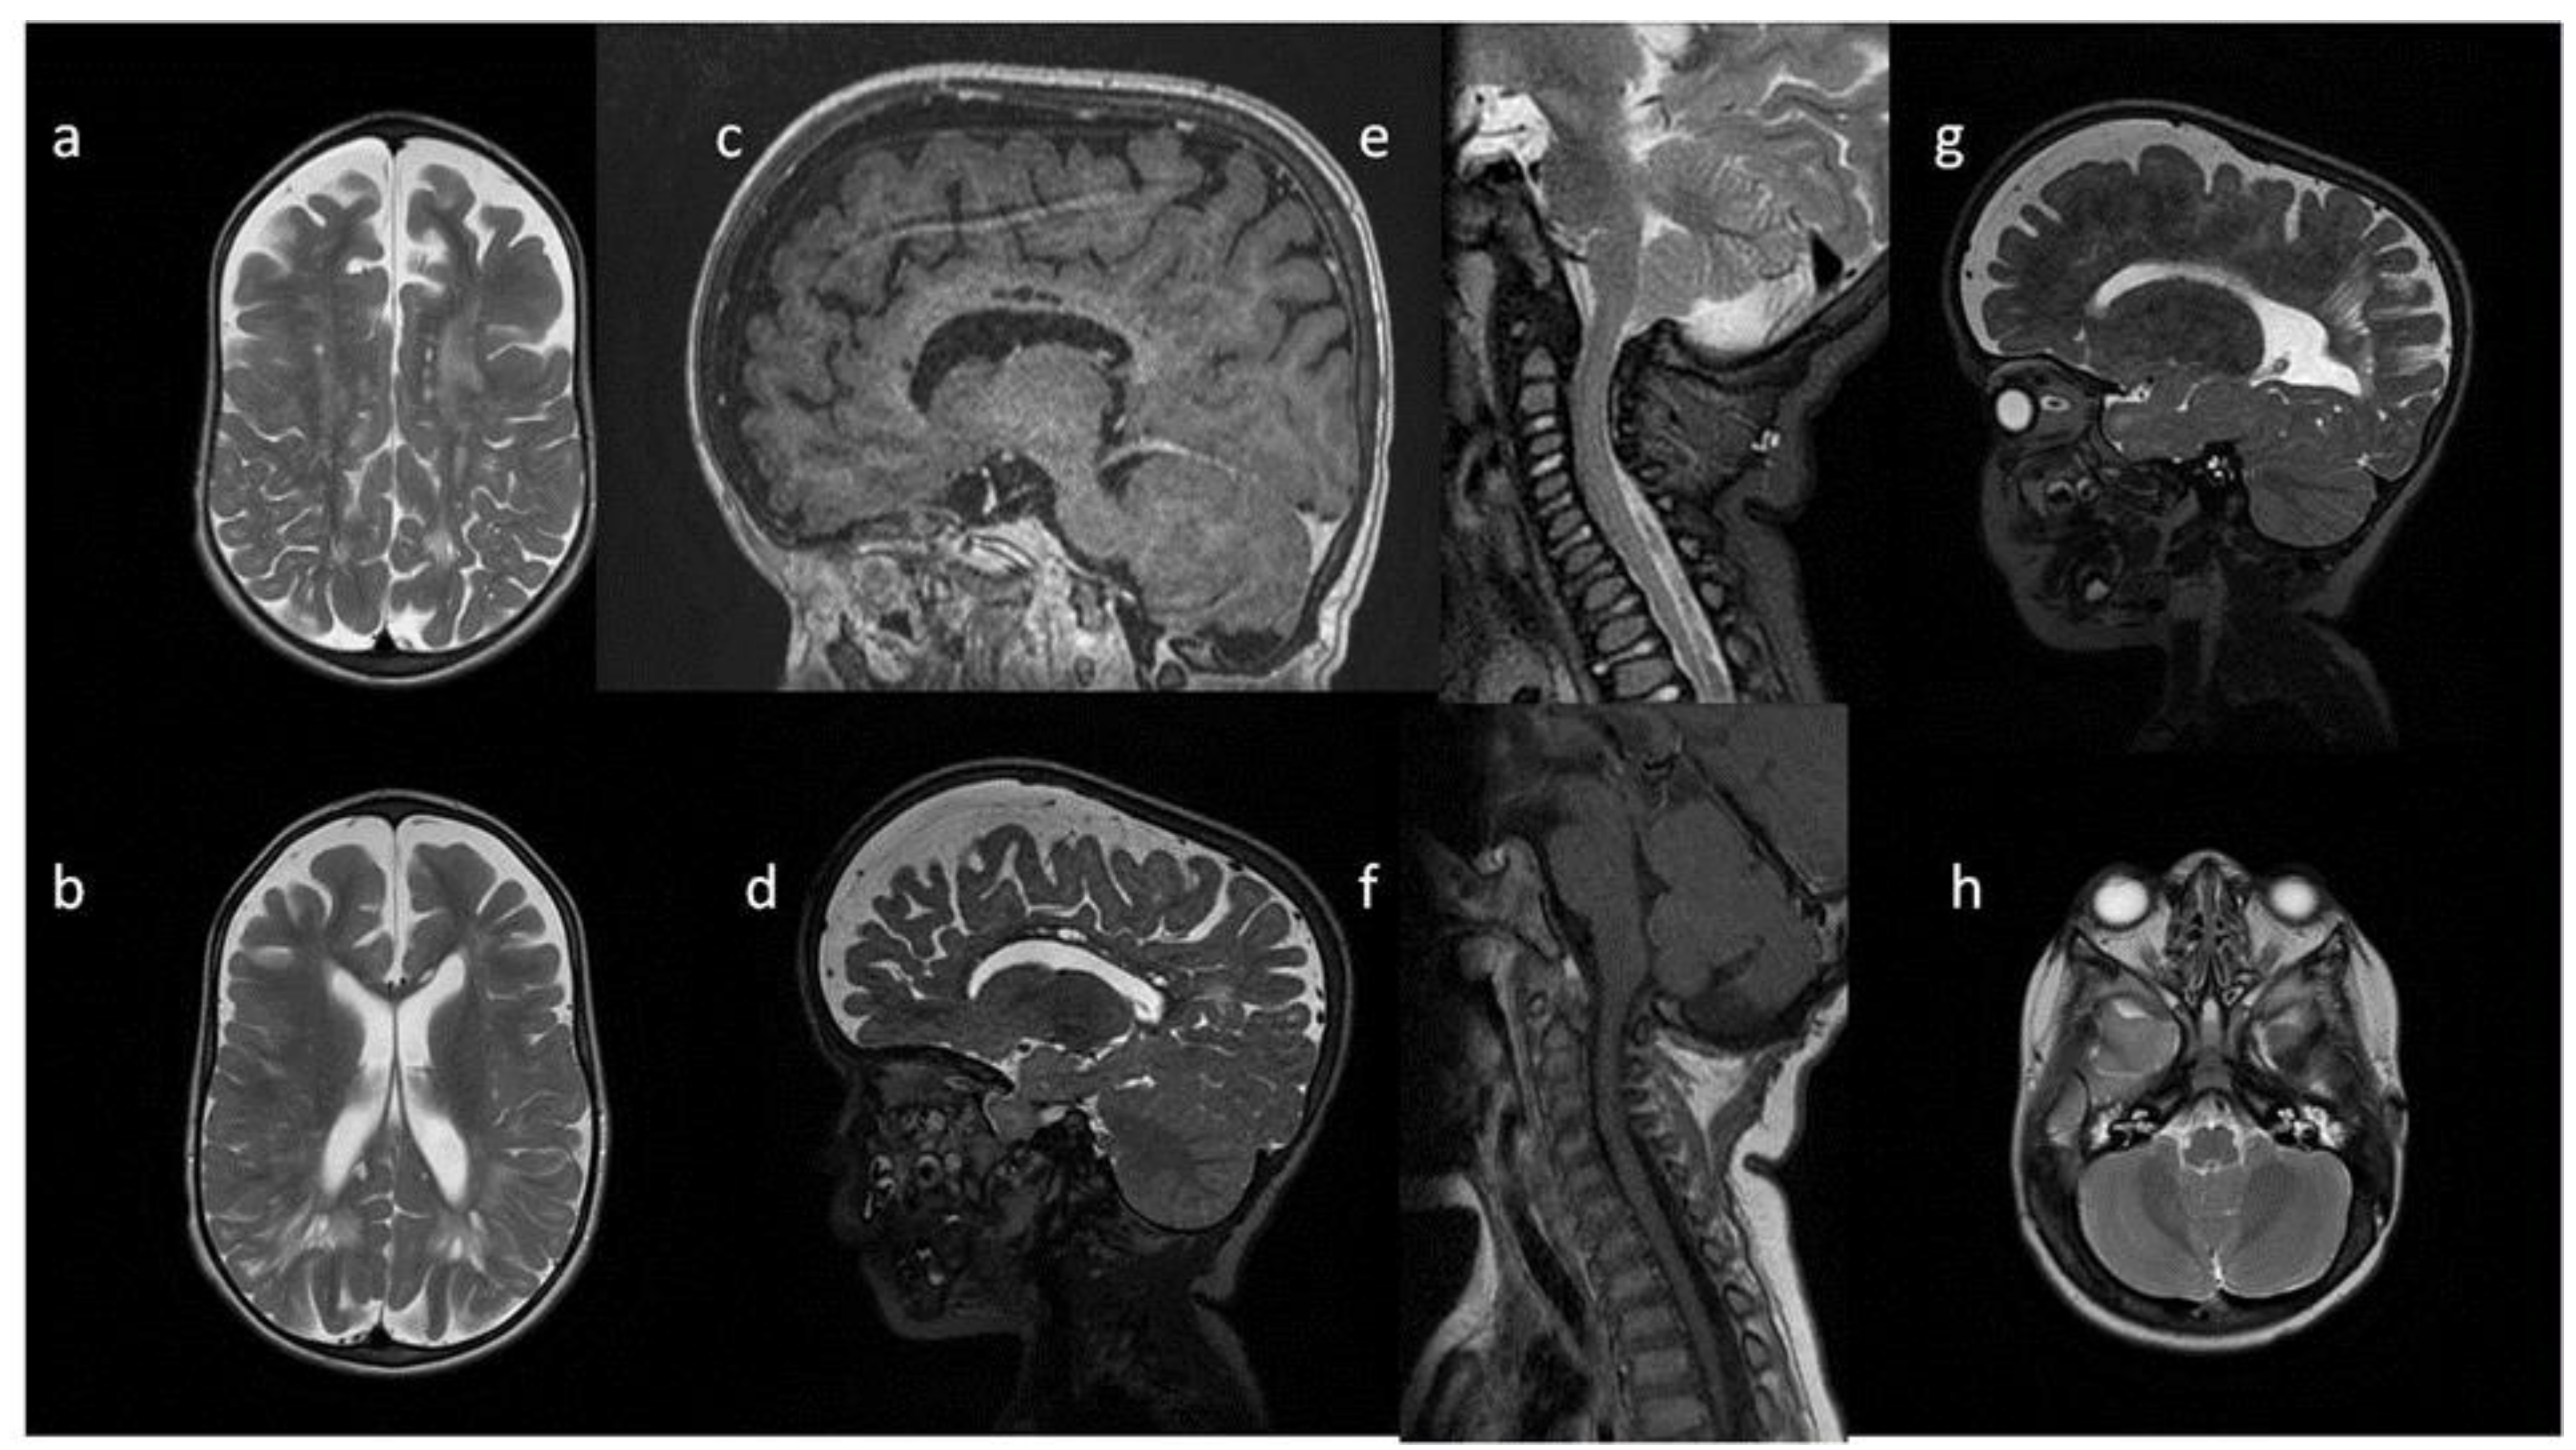

| Patient No | 1 | 2 | 3 | 4 | 5 | |

|---|---|---|---|---|---|---|

| age at exam | 4 mo | 3 yo | 1 y 2 mo | 1 y 11 mo | 3 y 2 mo | 14 yo |

| radiological imaging | ||||||

| WM signal abnormalities | + | + | + | |||

| areas of delayed myelination | + | + | + | + | + | |

| enlarged perivascular spaces | + | + | + | + | ||

| narrow corpus callosum | + | +/− | + | + | ||

| prominent ventricular system | +/− | + | +/− | + | + | |

| arachnoid cyst | + | + | ||||

| optic nerve sheath enlargement | + | + | ||||

| J-shaped sella turcica | + | + | + | +/− | + | +/− |

| craniocervical junction distortion | + | +/− | + | + | ||

| posterior fossa horns | + | + | + | + | ||

| fluid effusion temporal bone | + | + | + | + | +/− | |

| closed sagittal suture | + | + | + | |||

| vertebral bodies deformity | + | + | ||||

| intervertebral disc anomalies | + | + | ||||